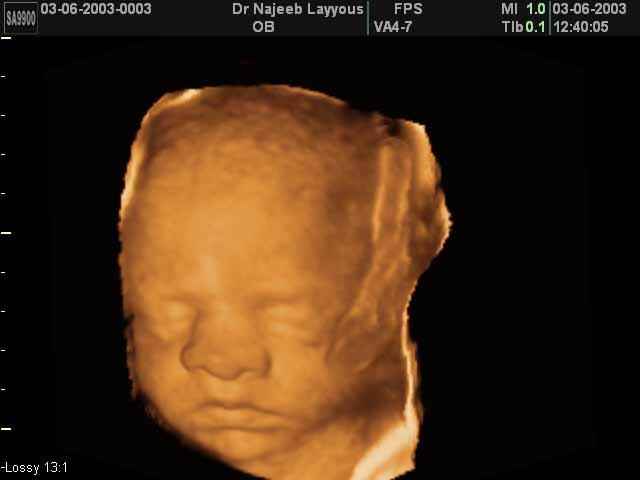

صور لوجه الجنين بجهاز الالتراساوند ثلاثي الأبعاد | الدكتور نجيب ليوس

صور لوجه الجنين بجهاز الموجات فوق صوتية ثلاثي الأبعاد